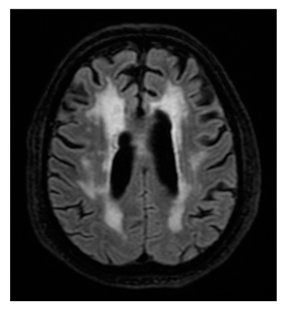

- Enlarged perivascular spaces (EPVS): Small (<3 mm) CSF-filled spaces, scored on a 0–4 scale for basal ganglia and centrum semiovale [22]. The values correspond to EPVS on a single hemisphere of the brain. In cases of asymmetry between hemispheres, EPVS were recorded in the slice with the maximum count, so that the higher score was accounted. EPVS total score for each patient was obtained by adding the scores from both regions (EPVS basal ganglia and EPVS semiovale), with a range of 0 to 8.

Regarding measurements of cerebrovascular disease, there were numerous statistically significant differences between MD and controls, namely the following: higher mean Fazekas score in MD (1.1 ± 0.8 in MD vs. 0.75 ± 0.8 in controls, p = 0.013); higher EPVStotal in MD (1.20 ± 0.9 in MD vs. 0.71 ± 0.8 in controls, p = 0.001);